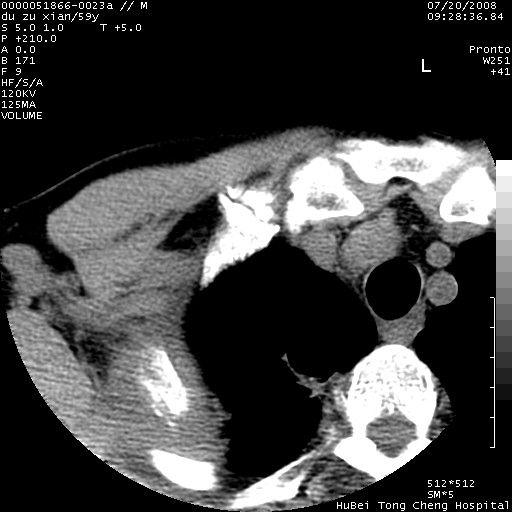

以下是引用宇宙ct在2008-8-25 23:21:00的发言:[br]右肺周围性肺癌并肋骨转移,纵隔淋巴结转移。

以下是引用zsl6918在2008-8-25 22:40:00的发言:[br]右肺周围性肺癌并肋骨转移,纵隔淋巴结转移。

以下是引用zy_zj在2008-8-26 15:24:00的发言:[br]单从病变本身,我倾向良性炎性病变,但肋骨转移了,所以说是考虑右肺周围性肺癌并肋骨、纵隔淋巴结转移可能性大。